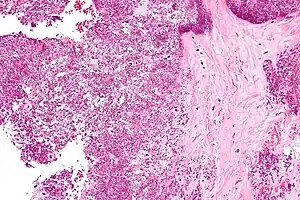

Cristais de Deposição De Pirofosfato De Cálcio Diidratado tendem a formar dentro de tecidos articulares. O diagnóstico é feito por microscópio, com a análise do fluido de uma junta. Radiografias da junta podem mostrar sinais de Condrocalcinose. Depósitos Assintomáticos podem se formar na cartilagem, articulações, discos intervertebrais, tendões e ligamentos. A deposição de cristais dentro da cartilagem (hialina e fibrocartilagem) é conhecido como condrocalcinose. É inicialmente só visível no microscópio, mas se houver bastante calcificação, pode ser visto com a ajuda da radiografia também. Locais comuns de condrocalcinose incluem os joelhos, punhos, cotovelos, e quadris.